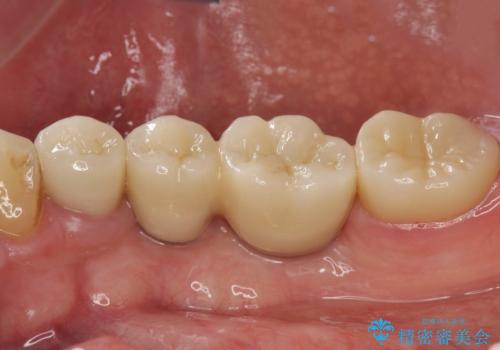

インプラント治療・セラミック治療を含む 全顎的虫歯治療

- 「 仕事が忙しく、虫歯を放置しすぎてしまった。この際全てきっちりと治したい。」と来院されました。

以上のような問題を、徹底的な虫歯治療、歯周外科、インプラント治療、部分矯正治療、精密根管治療を用いてひとつずつ解決ししっかりと長期的に食事を楽しめるような口腔内環境の再構築を目指します。